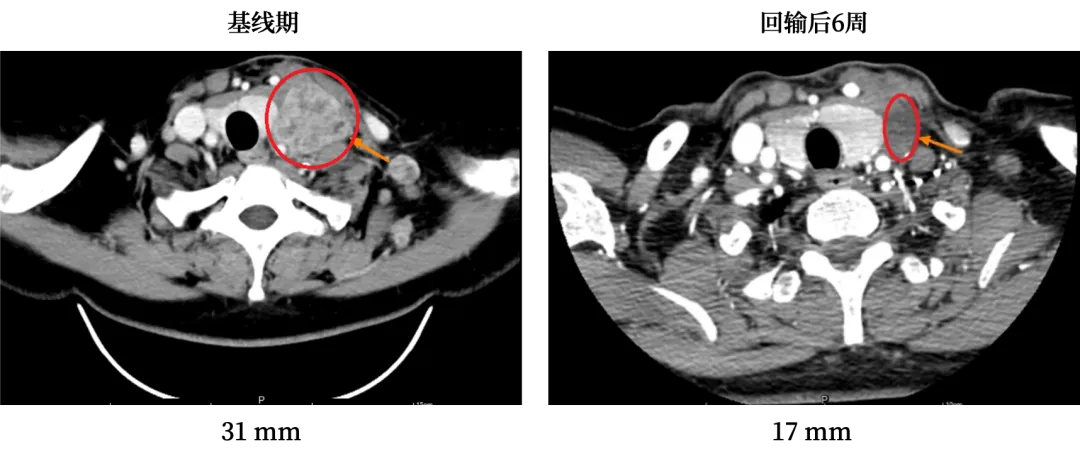

入组GC101 TIL临床试验后,他接受了单次细胞回输,仅出现短暂的一过性血象降低。42天疗效评估时,肿瘤缩小45%,癌胚抗原恢复正常,颈部肿大的淋巴结彻底消失,癌痛也随之缓解,重新燃起了活下去的希望。